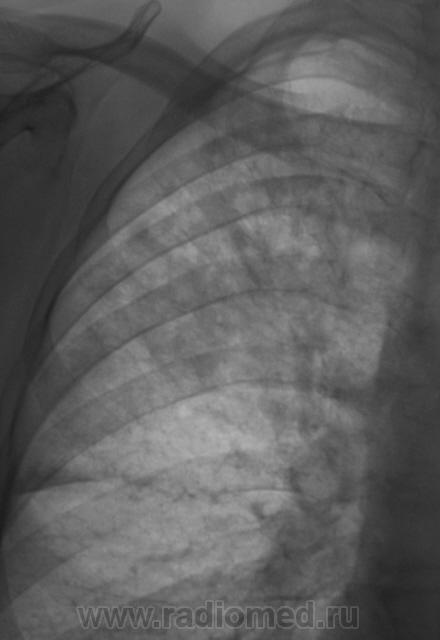

Пациент, при расшифровке флюорограмм, "взят на контроль". Произведено стандартное рентгенологическое исследование. Вот рентгенограмма.

Томограммы.

Ваше мнение уважаемые коллеги?